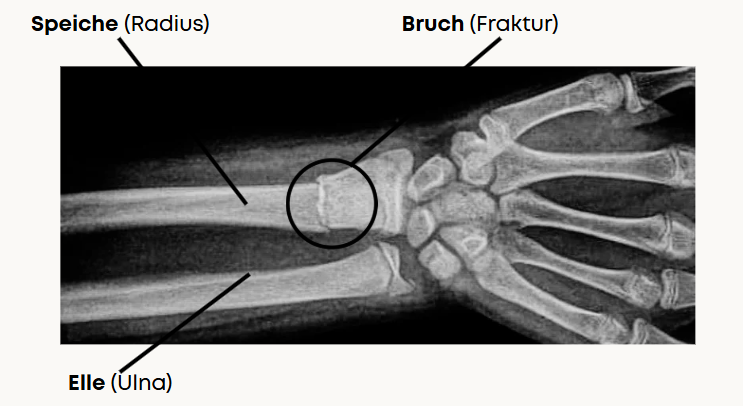

Unter einer distalen Radiusfraktur versteht man einen handgelenksnahen Bruch der Speiche (bis zu 3cm über dem Handgelenk).

Ergänzt wird der Sichtbefund sowie die Funktionsuntersuchung durch eine Röntgenaufnahme oder ein MRT (bei Verdacht auf Begleitverletzungen)